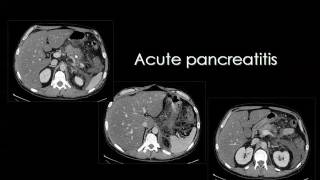

Cleveland Clinic Abu Dhabi Anatomy and CT Imaging of the Pancreas

Intended for an audience of medical students, this presentation explores the gross anatomy and radiographic findings related to the normal and the diseased ...